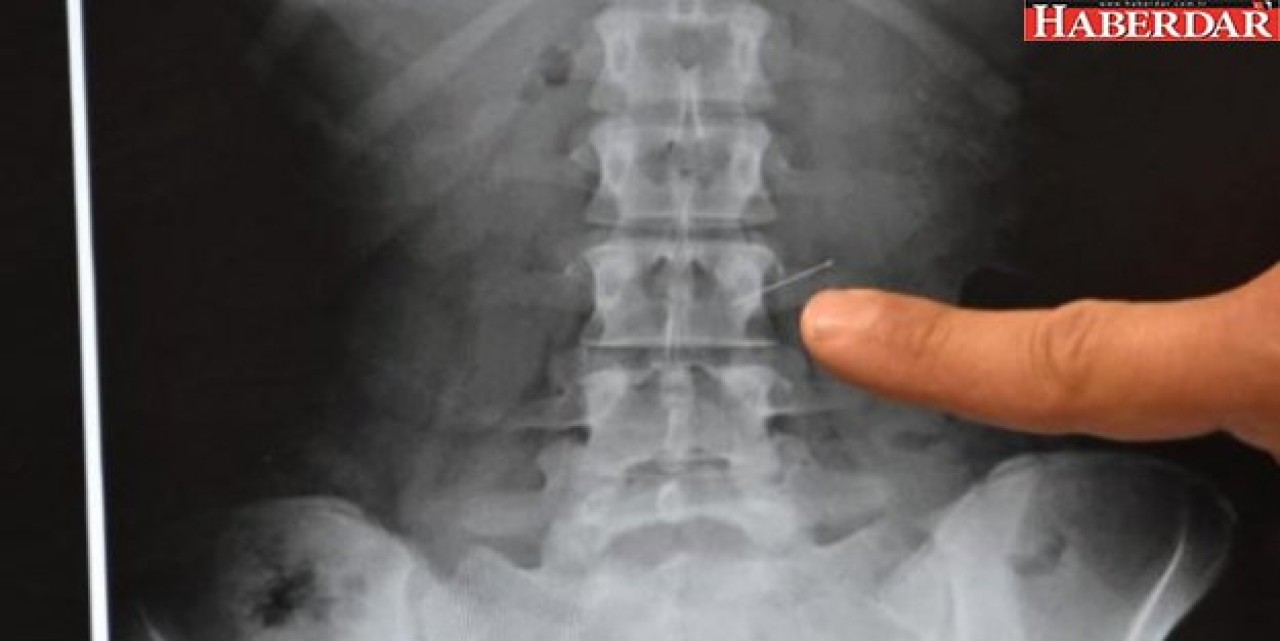

Konya'nın Ilgın İlçesi'nde 18 yaşındaki İlayda Adıgözel, kursa gitmek için hazırlanırken, eşarbını tutturmak için ağzında tuttuğu 3 toplu iğneden birini öksürünce yuttu. Hastaneye götürülen genç kızın midesindeki iğne yapılan operasyonla alındı.

Özel Farabi Hastanesi'ne getirilen genç kız hemen ameliyata alındı. Endoskopi yöntemiyle İlayda Adıgözel'in midesinde bulunan toplu iğne çıkartıldı. İlayda Adıgözel yaşadıklarını şöyle anlattı:

Operasyonu gerçekleştiren Genel Cerrahi Uzmanı Dr. Bülent Erenoğlu, "Bize vakit kaybetmeden geldi. Biz de endoskopiyle müdahale ettik ve iğneyi başarılı bir şekilde çıkardık. İğne birkaç yerde zedeleme yapmış, onun dışında bir problem yok" dedi.